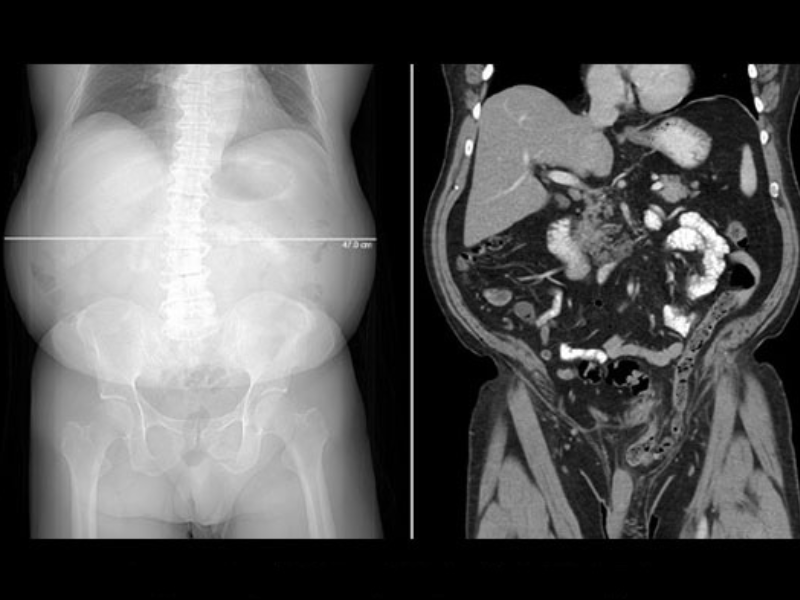

Bariatric abdomen/pelvis exam revels hernia